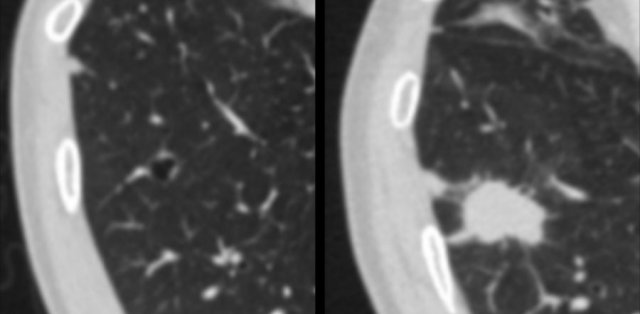

This example shows transition from part-solid (left panel), to temporarily cystic (middle panel), to solid lung cancer morphology (right panel).